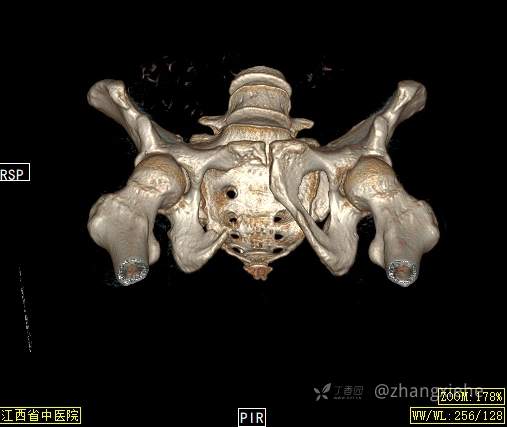

2022-03-05血常规示:血红蛋白:64g/L,生化示:白蛋白20g/L。骨髓涂片细胞学检查示:骨髓增生明显活跃,粒红比减低。粒、红、巨三系增生明显活跃。粒系伴成熟障碍。髓片浆细胞较易见,占7%。粒系增生明显活跃,核明显左移,可见巨幼样变及核浆发育不平衡。PET-CT示:1.右肺下叶软组织肿块、右侧耻骨下支及耻骨联合处骨质破坏伴软组织肿块形成,FDG代谢均异常增改,考虑恶性病变,建议病理检查;右侧髂血管旁、双侧腹股沟淋巴结反应性增生,建议随访。2.多浆膜腔(双侧胸腔、心包腔、盆腔)少量积液。3.全身骨骼FDG代谢弥漫增高,考虑骨髓反应性增生。4.大小肠条片状FDG代谢增高,考虑生理性摄取。5.右侧上颌窦面膜下囊肿,脑部FDG代谢未见明显异常。6.C7-T1层面后纵韧带钙化。患者乏力加重,卧床不起,不能承重,大小便不顺畅,转院至我院。门诊拟“1.右肺占位并右侧骨盆转移2.低蛋白血症3.中度贫血 4,血糖升高(原因待查)”收入住院。患者发病以来,无胸闷、胸痛,无呼吸困难,偶咳嗽,无咳血,饮食、睡眠欠佳,2个月之内体重减轻约10kg。

右骨盆及双下肢未见畸形,皮温正常,无浅静脉怒张,右腹股沟中点可触及一质韧肿物,大小约6cm*4cm*5cm,边界不清,固定、压痛明显,叩击痛阳性。右髋关节外旋、屈曲受限。右髋4字试验阳性,左侧阴性,双下肢直腿抬高试验阴性。感觉、运动正常,末梢血运良好,生理反射存在,病理反射未引出。

诊断?1.肺神经内分泌癌并右骨盆转移 ?2,骨盆透明细胞肉瘤并肺转移?3,多重癌(骨盆透明细胞肉瘤、肺神经内分泌癌) ?